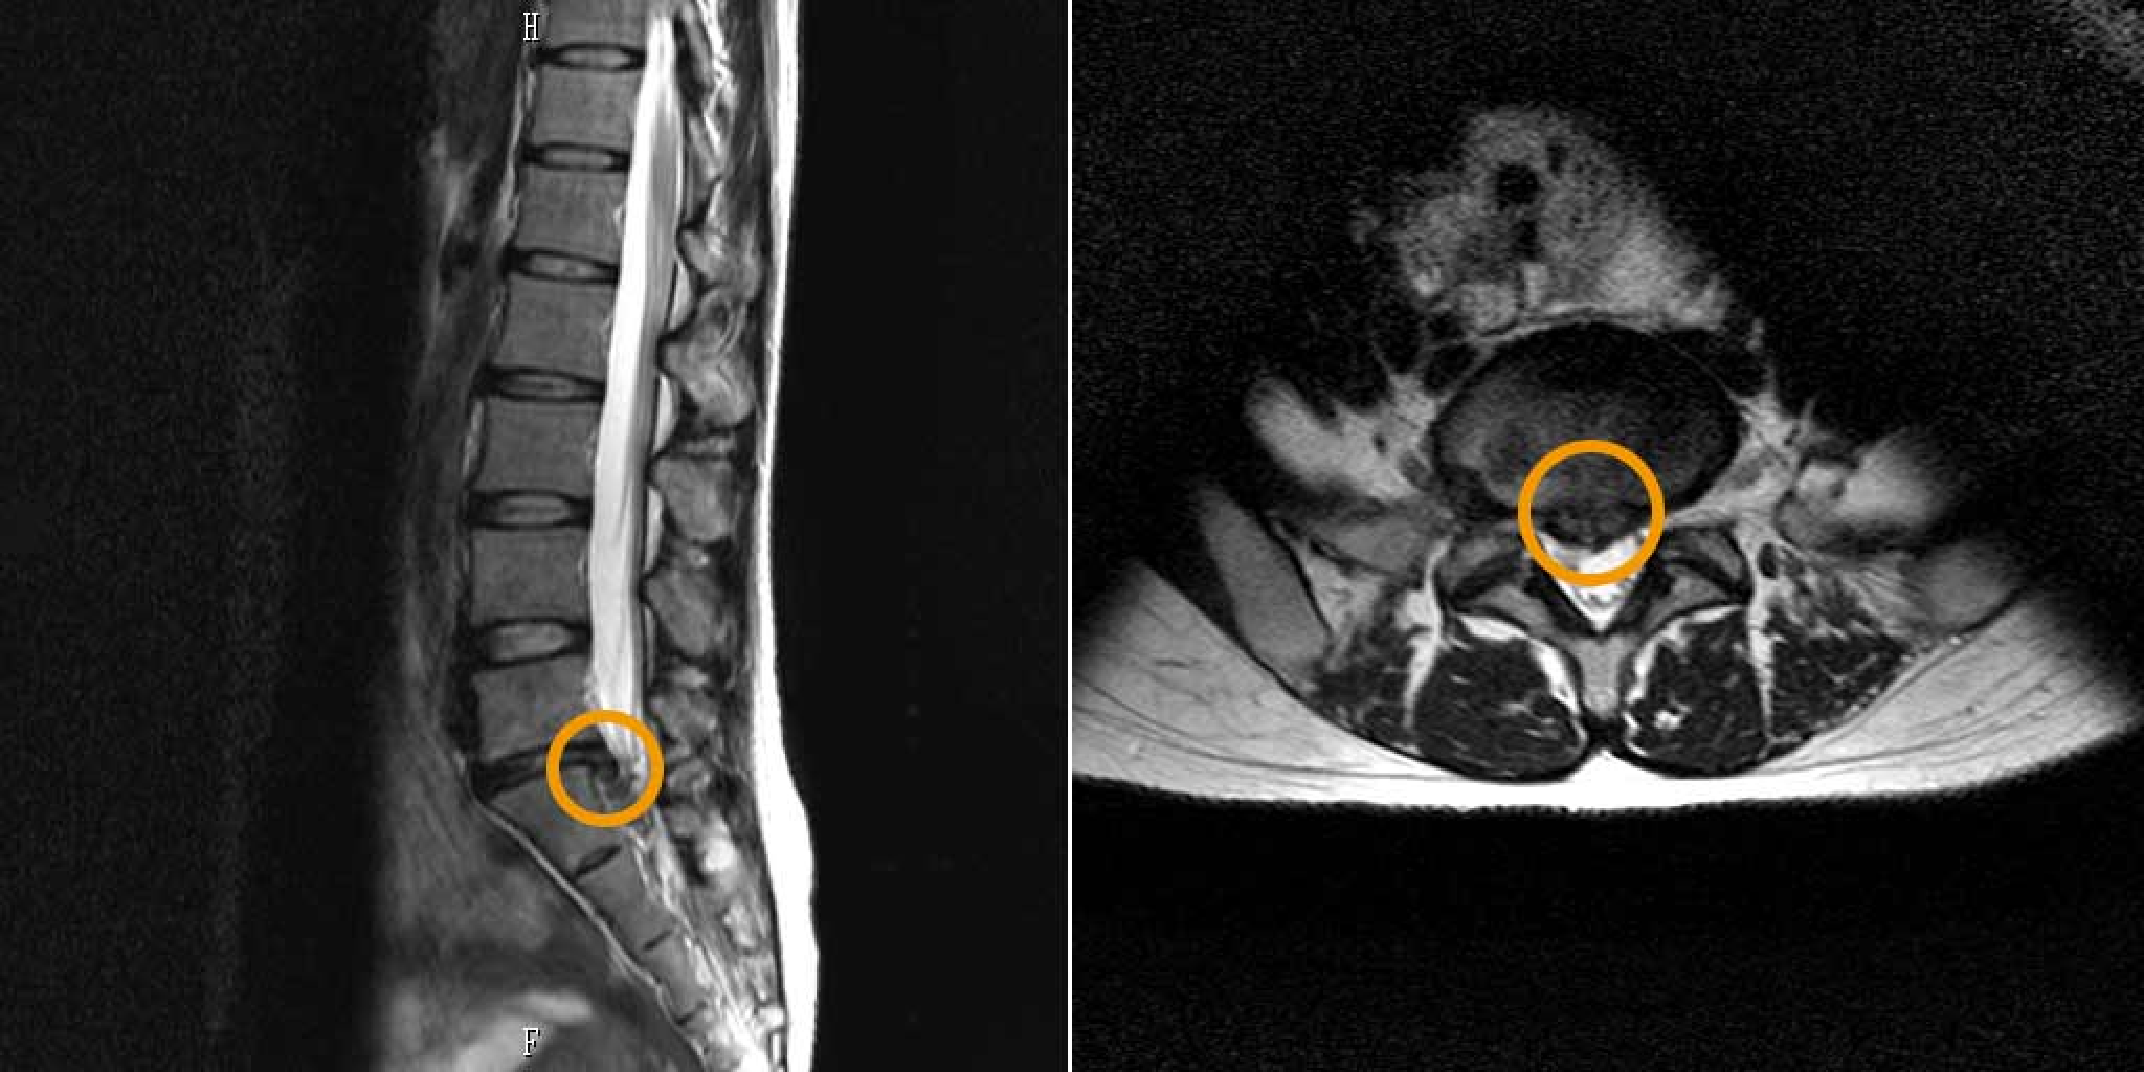

No.04 脊椎検査|

運動機能を守るための精密な脊椎検査矢印のイラスト

脊椎疾患の早期発見と予防管理

脊椎(背骨)は、二足歩行をする人類にとって重要な役割を果たしていますが、

加齢や日常のストレスにより、頚椎症や椎間板ヘルニアなどさまざまな脊椎疾患が引き起こされる可能性があります。

当院では、MRIによる詳細な脊椎検査を実施し、これらの病気を早期に発見し、適切に対処します。

脊椎検査の重要性

頚椎や腰部に起こる障害は、腰痛症や脊椎管狭窄症など、老年期の生活の質に大きな影響を与える病気です。

MRIを使用した詳細な検査により、脊椎の状態を把握し、運動機能を維持するための予防管理を行います。

MRIによる精密検査

正常時頚椎とストレートネック

脊椎検査のイメージ画像

生活の質を守るための予防と治療

脊椎の病気は、日々の運動機能に影響を及ぼすため、早期に発見し適切な治療を行うことが重要です。

当院の脊椎検査は、痛みのないMRI検査で短時間に完了し、生活の質を守るための重要な情報を提供します。